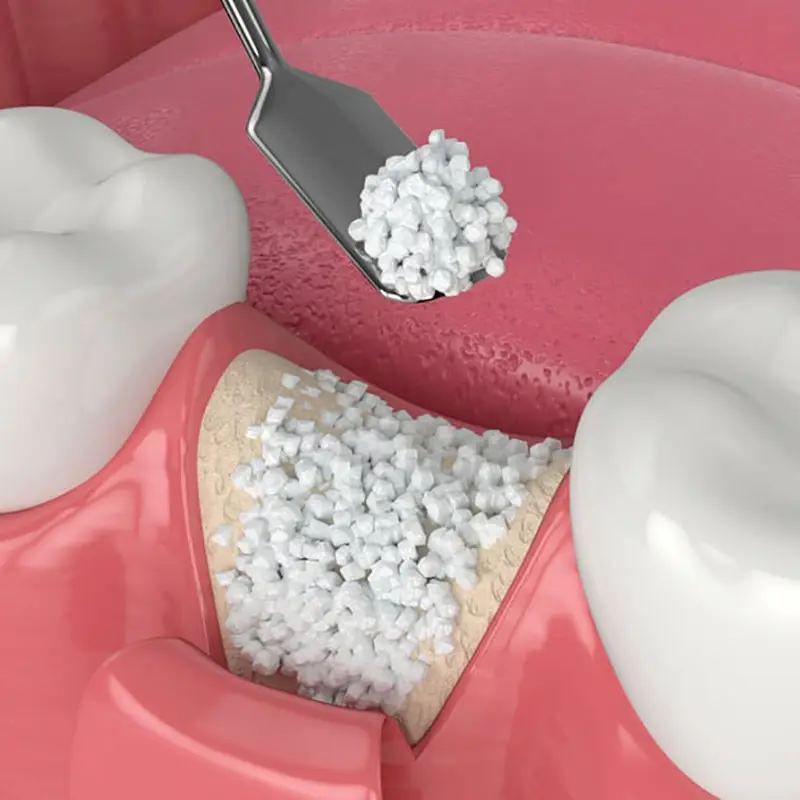

Il rialzo del seno mascellare, è una procedura chirurgica utilizzata per aumentare la quantità di osso disponibile nella parte posteriore dell’arcata dentale superiore.

Il rialzo del seno mascellare è necessario per i pazienti che hanno subito una perdita ossea nella zona posteriore dell’arcata dentale superiore a causa della mancanza di denti o per altre ragioni.